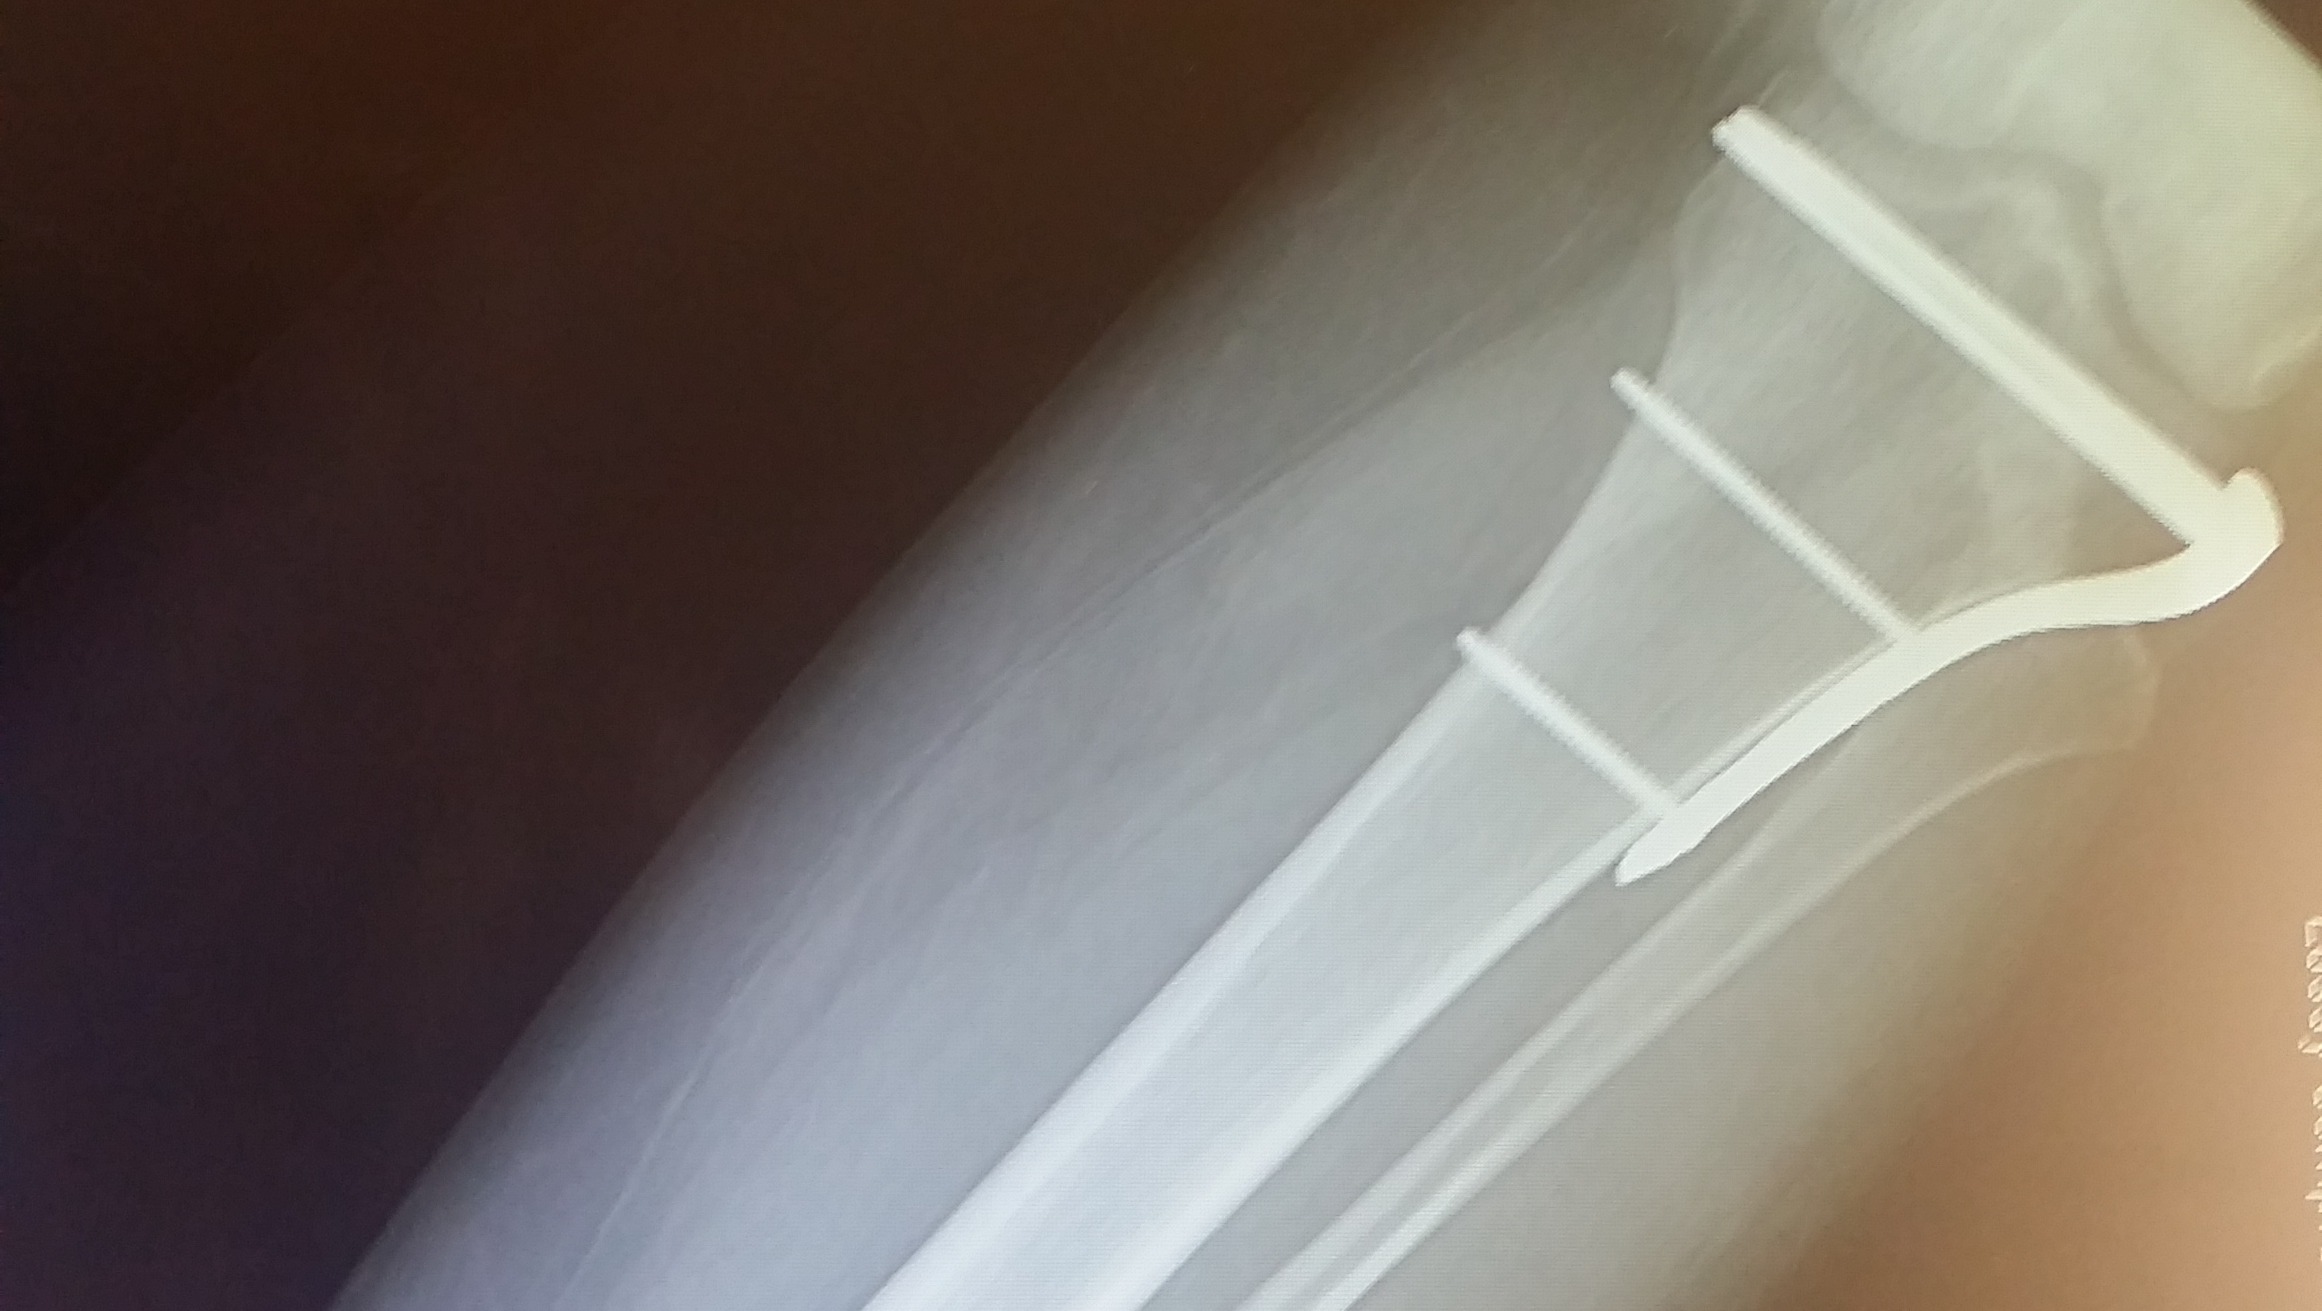

In June 2017, I took a severe fall and fractured my tibia. Once again, I went in for emergency surgery on my knee.

This surgery was very involved, and the fracture was so severe that human ligaments were donated to help me be able to walk again. I was told not to put weigh on that leg for six months. The pain I still feel on this knee can be unbearable some days